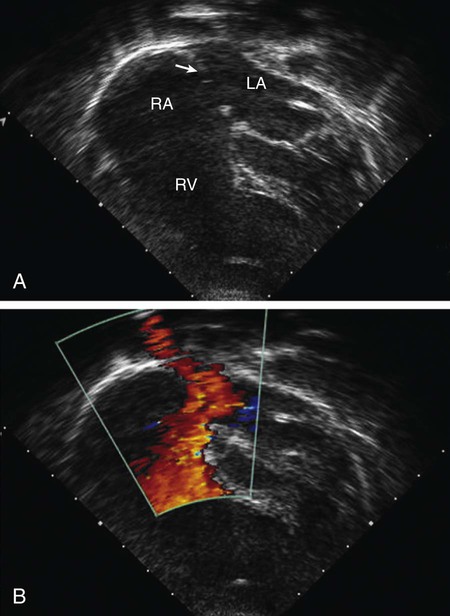

The echocardiogram shows findings characteristic of right ventricular volume overload, including an increased right ventricular end-diastolic dimension and flattening and abnormal motion of the ventricular septum (Fig. 426-2). A normal septum moves posteriorly during systole and anteriorly during diastole. With right ventricular overload and normal pulmonary vascular resistance, septal motion is either flattened or reversed—that is, anterior movement in systole. The location and size of the atrial defect are readily appreciated by 2-dimensional scanning, with a characteristic brightening of the echo image seen at the edge of the defect (T-artifact). The shunt is confirmed by pulsed and color flow Doppler. The normal entry of all pulmonary veins into the left atrium should be confirmed.